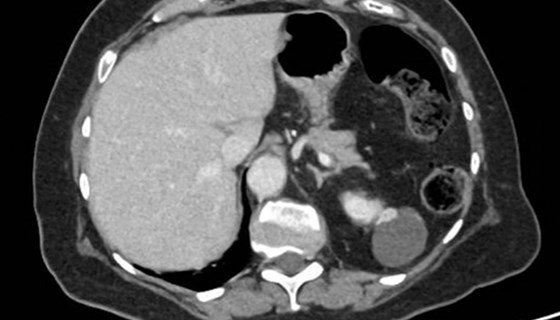

Urolithiasis related complications are estimated to affect between 1:200 and 1:2000 pregnancies [1,2]. With around 825,000 conceptions in England and Wales in 2021 [3], this represents an uncommon but not rare occurrence. What is normally a straightforward pathway for a...